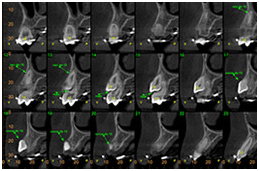

Avaliar fraturas radiculares Avaliar fraturas radiculares